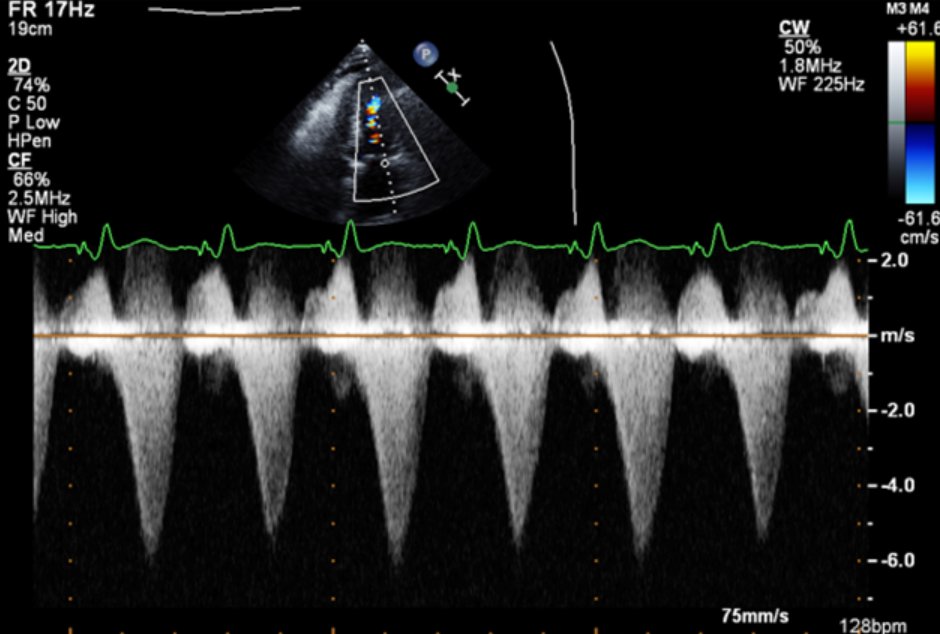

#CriticalCareQuiz A 75-year-old man has urosepsis; no prior history. BP 95/52, HR 124, lactate 6. TTE shows EF 75%. VTI is 60 cm from pulsed wave Doppler. LVOT diameter is 2 cm, which yields CO 23.4 L/min. MV CW Doppler is also shown. Why is CO so high? #SCCMSoMe

A 75-year-old man has urosepsis; no prior history. BP 95/52, HR 124, lactate 6. TTE shows EF 75%. VTI is 60 cm from pulsed wave Doppler. LVOT diameter is 2 cm, which yields CO 23.4 L/min. MV CW Doppler is also shown. Why is CO so high?